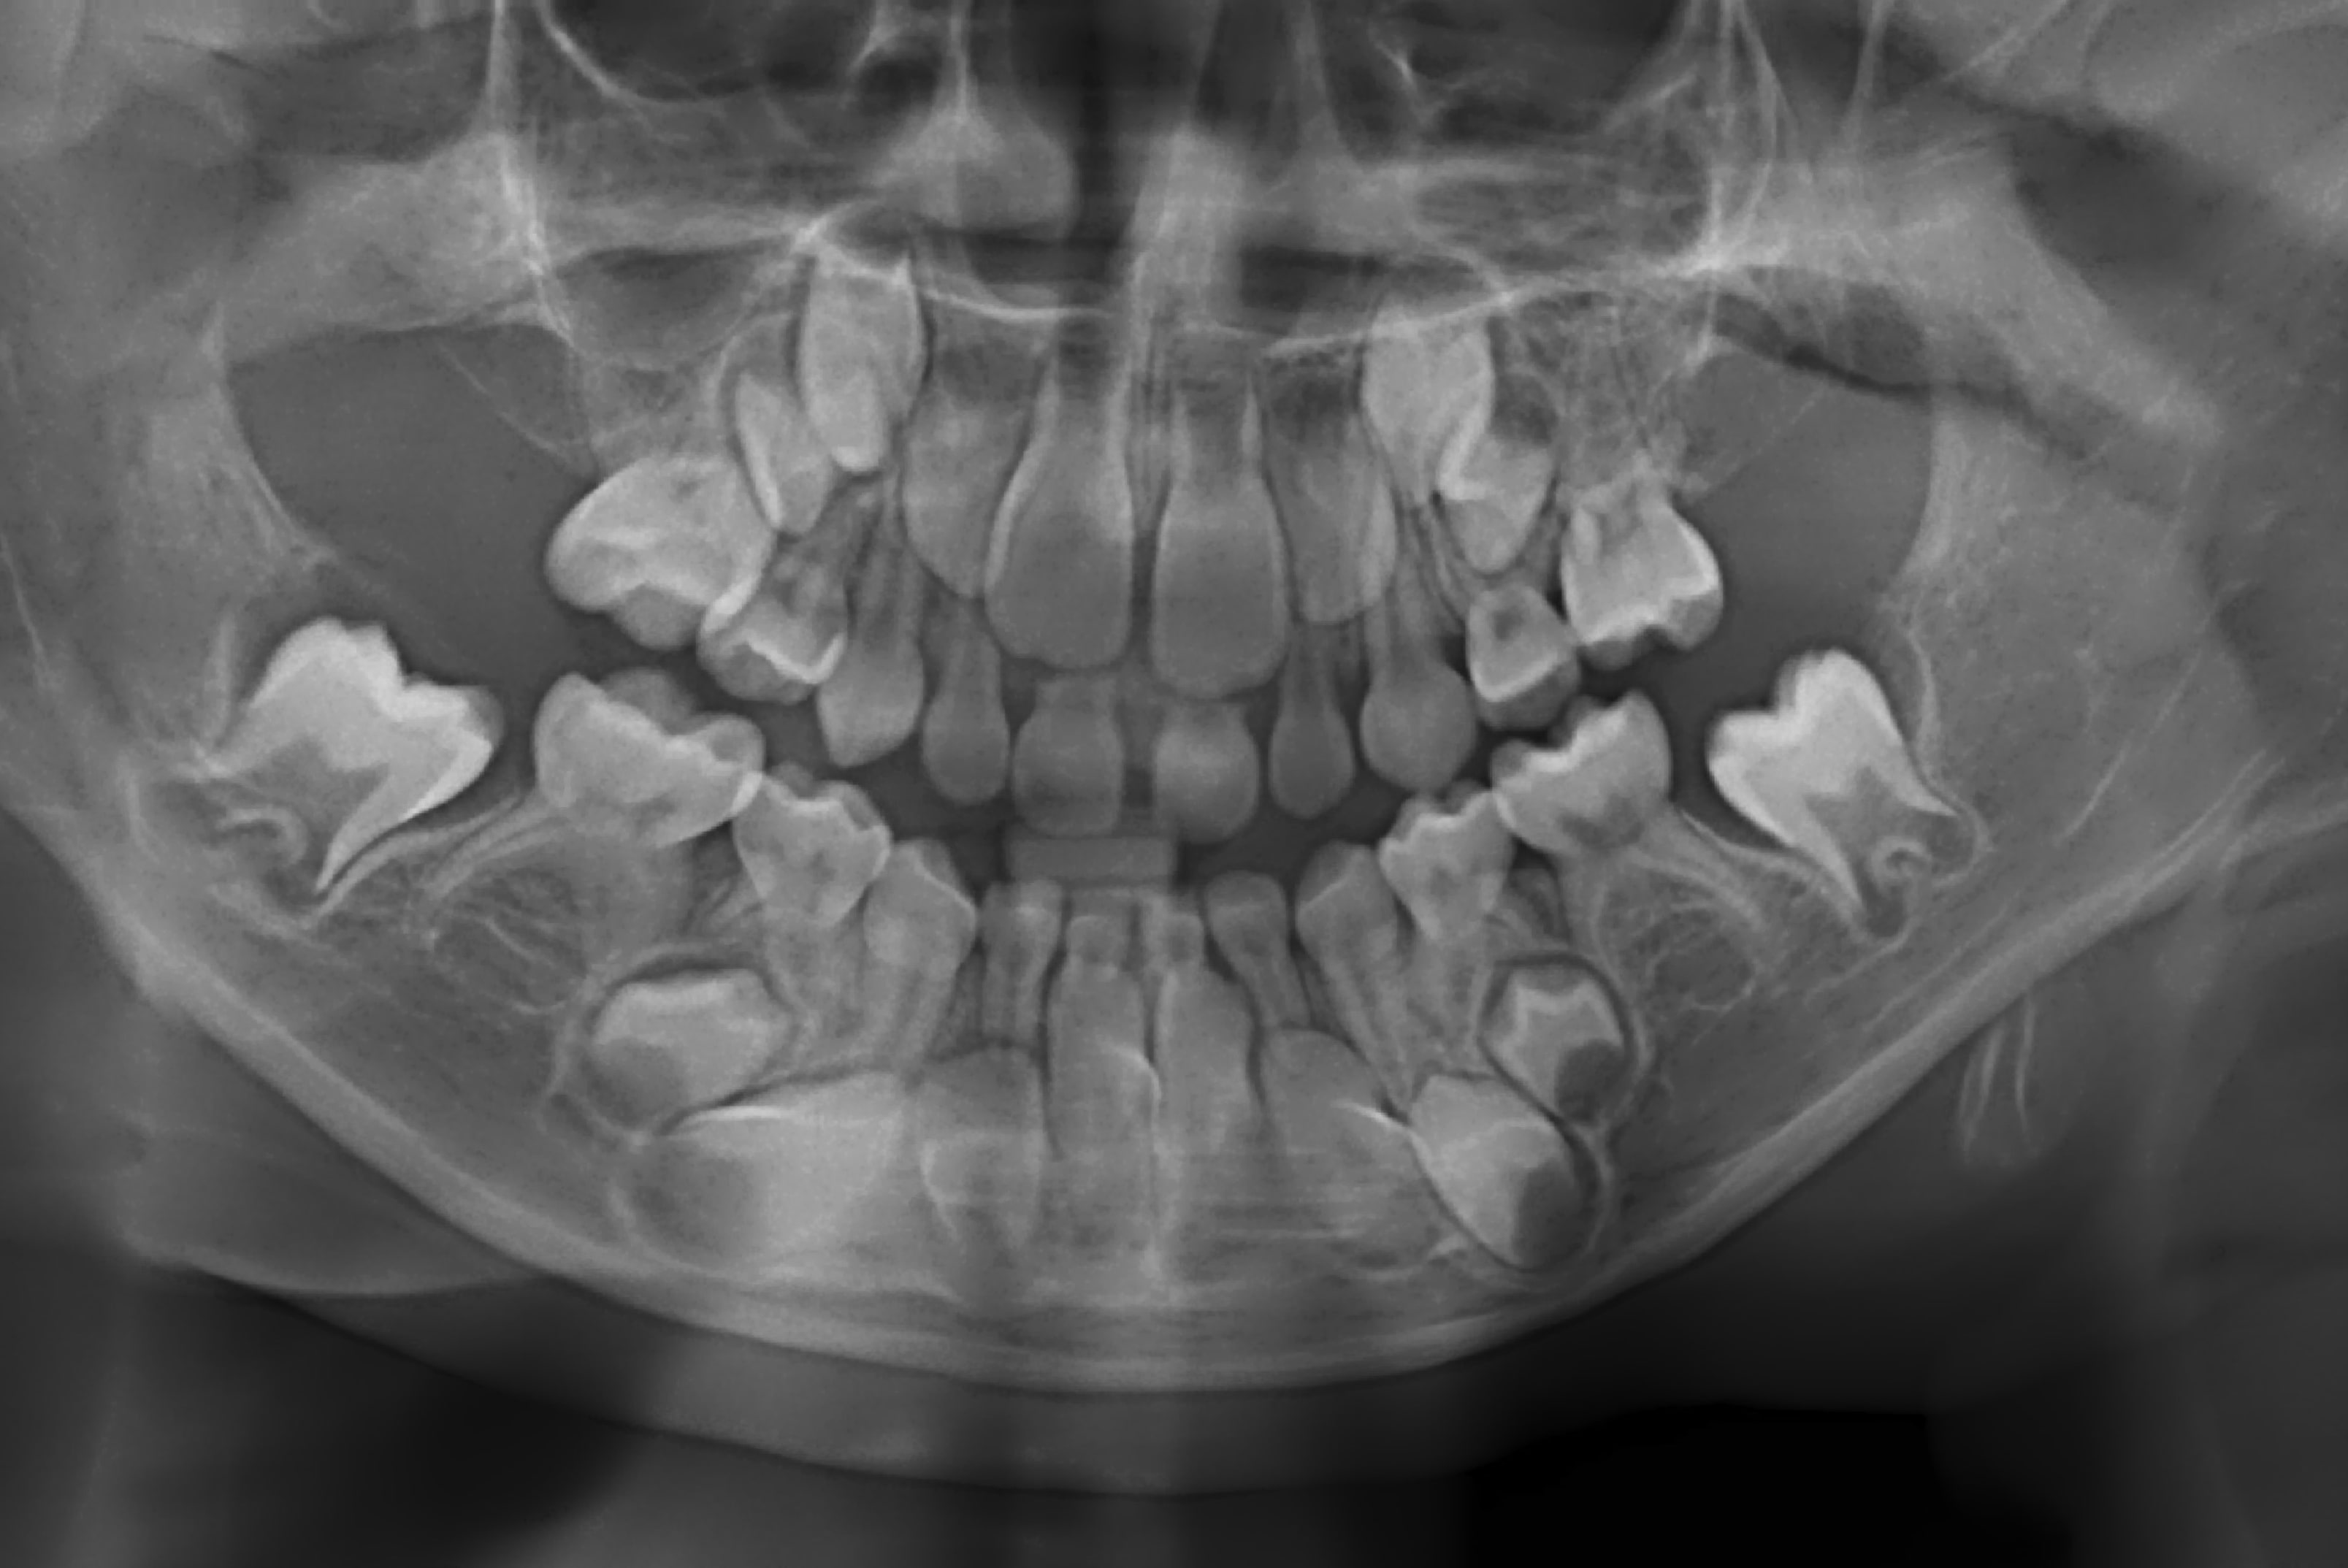

Voici le cas d'un petit patient de 6 ans venu au cabinet ce jour pour son premier rdv chez le dentiste, le patient n'a pas de problème de santé ni de syndrome particulier.. Pas de souci dentaire dans la famille (un peu de paro mais rien de catastrophique).

Sauf qu'à la pano, je vois qu'il manque plusieurs dents définitives (les 5, les 6 au mx ainsi que les 7).

on dirait qu'on distingue des lacunes au niveau des 5 et des 6 mx. on dirait plutôt un retard que des agénésies.

Prier pour l'apparition de germes de 8 dans quelques années, pourquoi pas des 7 un peu en retard (l'éruption des autres ne semble pas pressée.)

Pour les 5 je ne vois rien, pour les 6 justement je parie plus sur des 7 étant donné le stade évolutif. Mais je les vois également.

Je voyais un genre de lacune/liseré sous les racines des 5 mais un sacré doute m’a prise. Dans l’idéal, il faudrait revoir le patient d’ici 1 an et voir si les germes se sont développés. Et si à ce moment y’a toujours rien, ça vaudrait pas le coup de l’envoyer en consultation spé ?

Sethef l’indication de la pano visait justement à apprécier la présence des germes des définitives, car si à la mandibule la gencive en arrière des 5 lacteales avait un aspect bien tuméfié comme lorsque une dent va sortir, ça n’était pas le cas haut où l’arcade s’arrête nette juste en arrière des 5